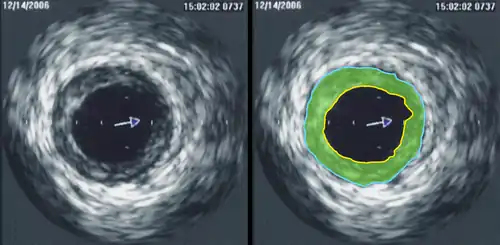

Intravascular ultrasound (IVUS) or intravascular echocardiography is a medical imaging methodology using a specially designed catheter with a miniaturized ultrasound probe attached to the distal end of the catheter. The proximal end of the catheter is attached to computerized ultrasound equipment. It allows the application of ultrasound technology, such as piezoelectric transducer or CMUT, to see from inside blood vessels out through the surrounding blood column, visualizing the endothelium (inner wall) of blood vessels.[1]

The (a) blood vessel wall inner lining, (b) atheromatous disease within the wall and (c) connective tissues covering the outer surface of the blood vessel are echogenic, i.e. they return echoes making them visible on the ultrasound display.

By contrast, the blood itself and the healthy muscular tissue portion of the blood vessel wall is relatively echolucent, just black circular spaces, in the images.

Heavy calcium deposits in the blood vessel wall both heavily reflect sound, i.e. are very echogenic, but are also distinguishable by shadowing. Heavy calcification blocks sound transmission beyond and so, in the echo images, are seen as both very bright areas but with black shadows behind (from the vantage point of the catheter tip emitting the ultrasound waves).